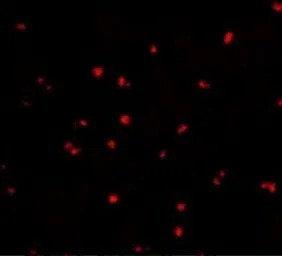

ICC/IF analysis of Jurkat cells using GTX31664 NOD2 antibody.

Working concentration : 5 μg/ml

Working concentration : 20 μg/ml